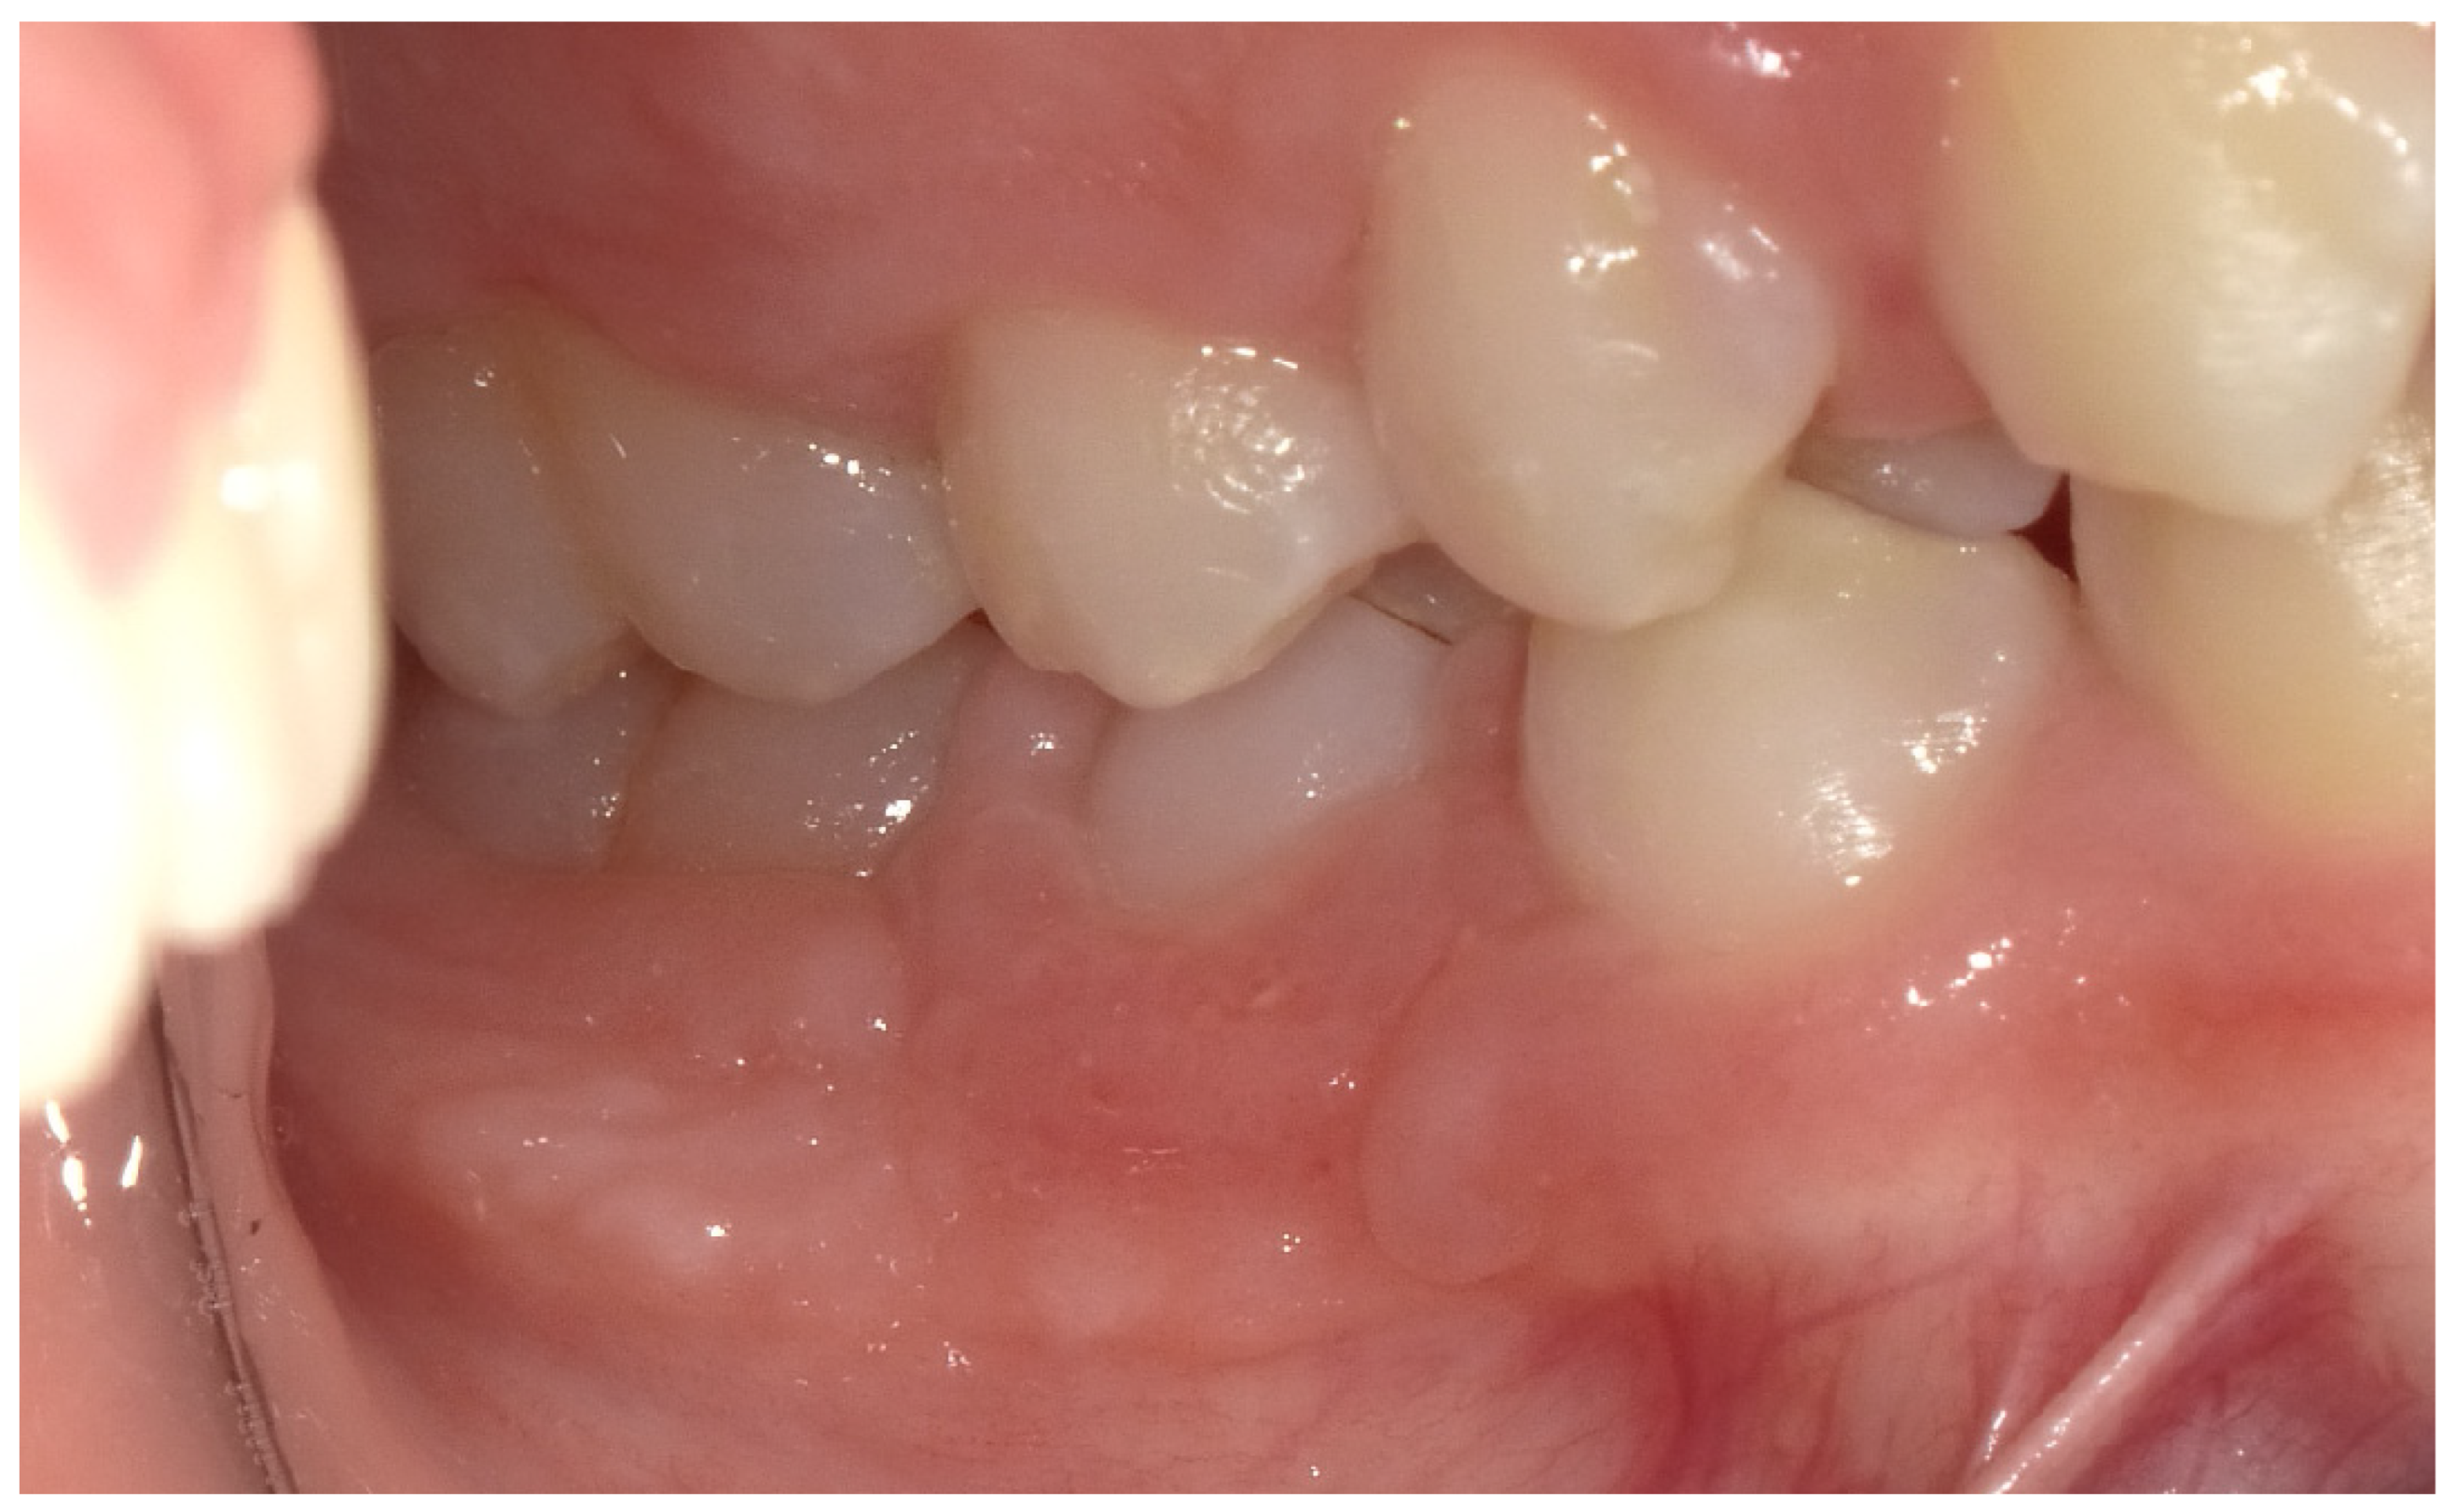

2.2. Clinical Findings

2.3. Diagnostic Assessment

2.4. Therapeutic Intervention

2.5. Follow-Up and Outcomes